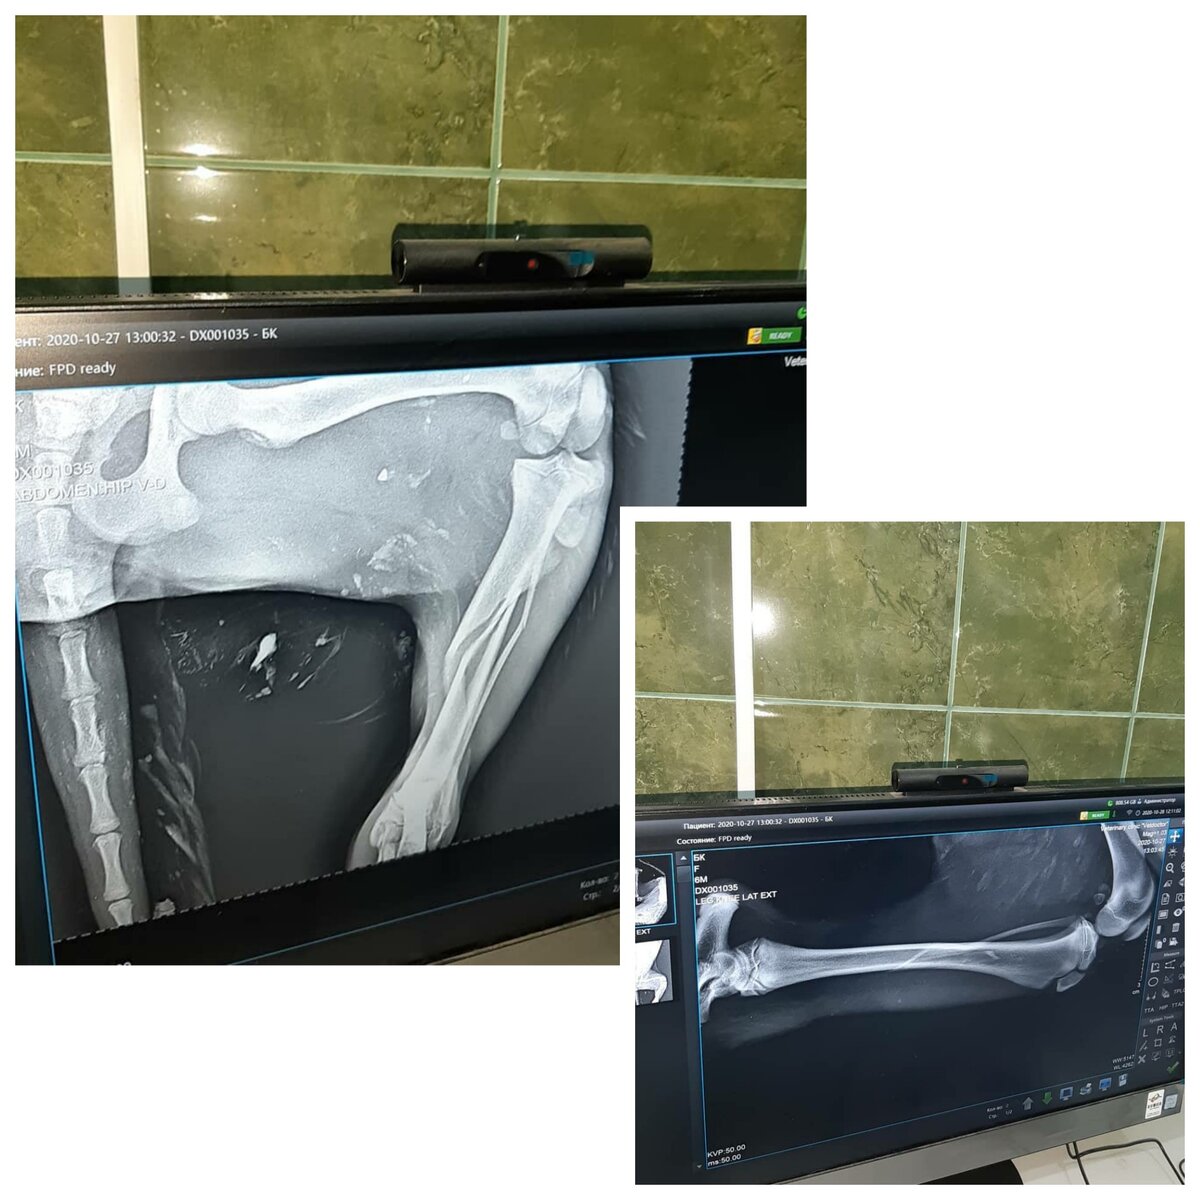

По результату рентгена - перелом задней лапы, сильный ушиб. Собачка еще ребенок примерно полгода, косточки молодые и есть шанс, что лапа срастётся и без операции. Сейчас малышке нужно тёплое местечко и ограничить ее в движении, поколоть уколы антибиотики, обезболивающие и через 2 недели показаться в клинике.

Рентген лапы

При осмотре в клинике проблему с задней лапой подтвердили. Сделали рентген и стало понятно, что пострадала вся правая сторона. Перелом и передней и задней лапы.

Рентген

Оперировать в первую очередь нужно переднюю лапу так как она является опорной. Затем восстановительный период и операция на заднюю лапку.